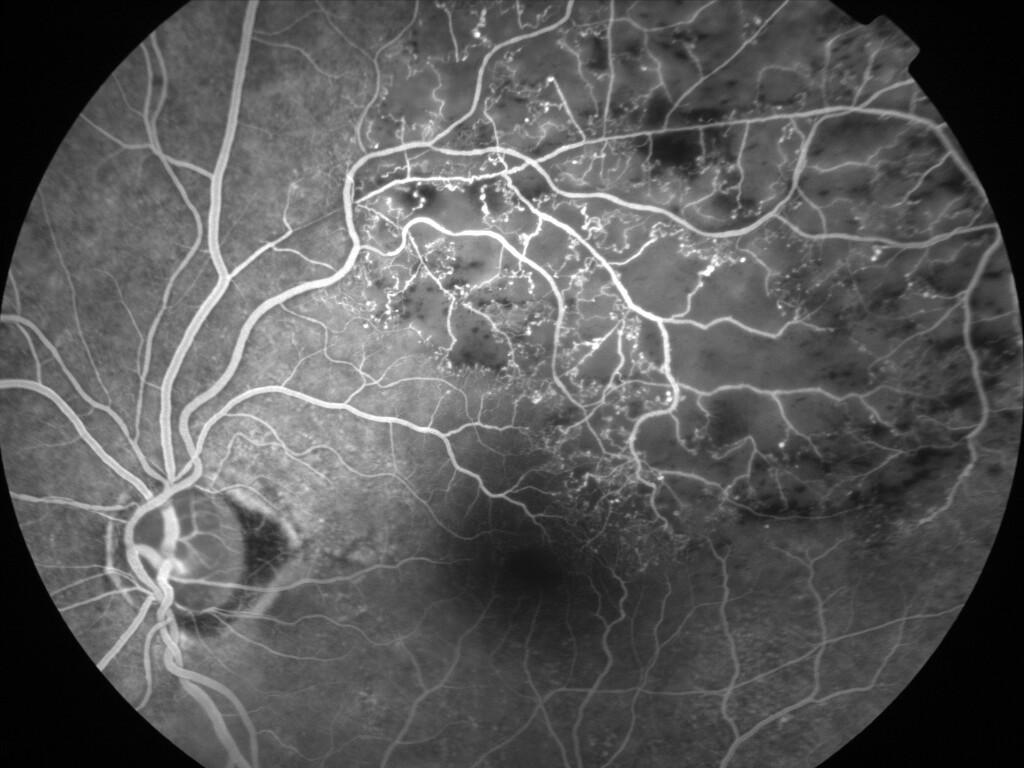

OCCLUSION DE BRANCHE DE LA VTS DE FORME ISCHEMIQUE MAJEURE